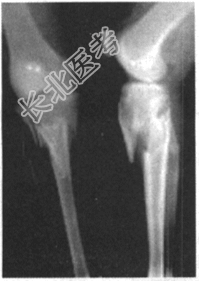

- [材料题] 患者,男性,65岁。因车祸致伤左小腿后肿胀、活动受限、疼痛2小时。查体:左小腿上端肿胀,触痛(+),触及骨擦音,左足伸足、伸趾功能正常,足背动脉搏动正常。

- 多项选择题1.提示:该患者X线片如下图。该患者的正确诊断为

A、左胫骨平台粉碎性骨折,左腓骨上段骨折

F、左胫腓骨上段双骨折